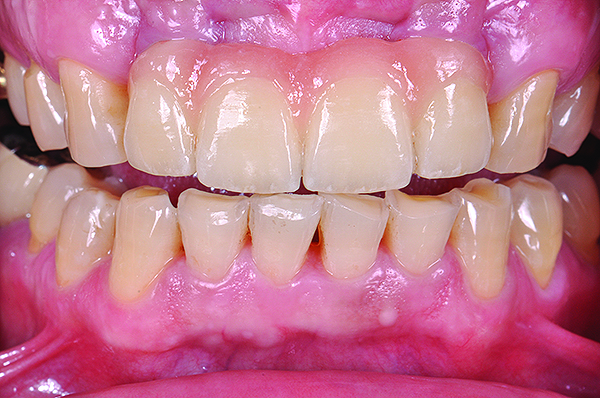

Fig 5. Preoperative view of patient requiring esthetic changes up to at least the bicuspids (Fig 5); postoperative view with CL-I feldspathic porcelain veneers up to the first bicuspid (Fig 6).

Figure 5

Fig 6. Preoperative view of patient requiring esthetic changes up to at least the bicuspids (Fig 5); postoperative view with CL-I feldspathic porcelain veneers up to the first bicuspid (Fig 6).

Figure 6